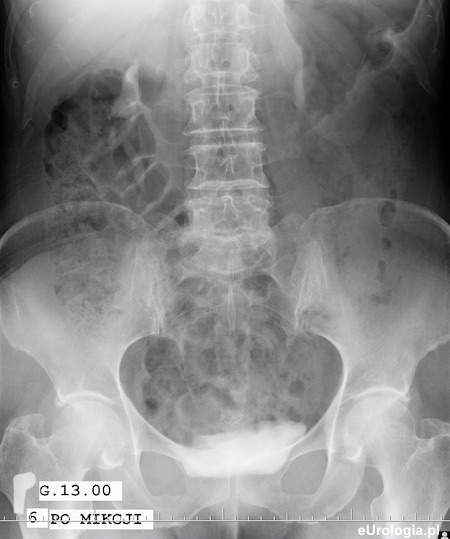

Zdjęcie urograficzne po mikcji - widoczny zalegający w pęcherzu zakontrastowany mocz